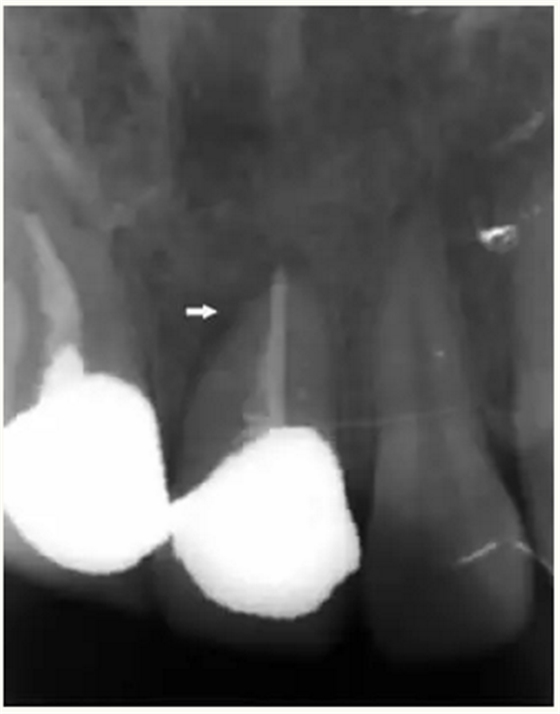

▲ 术前,21唇侧牙龈距离龈缘2mm处及瘘管

▲牙胶尖示踪显示瘘管与此相通

▲21牙根近中侧位于根尖1/3和根中1/3交界处有牙周膜间隙略增宽